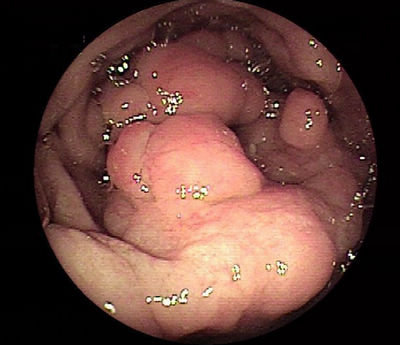

息肉

息肉(polyp)一词可泛指粘膜表面的隆起,包括粘膜息肉和粘膜下(息肉样隆起)病变。

粘膜息肉又可分为肿瘤性息肉(包括腺瘤或癌)和非肿瘤性息肉。一般地,息肉是指粘膜息肉,其中不包括肉眼即可诊断为恶性肿瘤的肿瘤性息肉。

腺瘤性息肉

腺瘤性息肉可分为管状腺瘤、绒毛状腺瘤、管状绒毛状腺瘤和锯齿状腺瘤。

管状腺瘤多颜色较深,表面光滑。绒毛状腺瘤约占腺瘤的5%,常见于老年人,多比较大、无蒂,表面粗糙、呈菜花样或分叶状,通常质地较脆。

管状绒毛状腺瘤含有管状腺瘤和至少25%的绒毛状腺瘤,其临床表现介于两者之间。

锯齿状腺瘤仅占大肠息肉的不足1%,发生高度不典型增生的比率却高达40%,其结构类似增生性息肉,但混有腺瘤或腺体增生的表现。

非肿瘤息肉

非肿瘤息肉包括增生性息肉、炎性息肉和错构瘤性息肉等。

增生性息肉的发生率仅次于腺瘤性息肉,多小于5 mm、无蒂,颜色较淡,多位于直肠和乙状结肠。增生性息肉不是癌前病变。

炎性息肉见于溃疡性结肠炎、克罗恩病、缺血性结肠炎、血吸虫病等结肠粘膜的重度炎性疾病。

如果息肉由残存的岛样结肠上皮构成,则常被称为假息肉(pseudopolyps)。错构瘤性息肉包括Peutz-Jeghers息肉和幼年性息肉等。